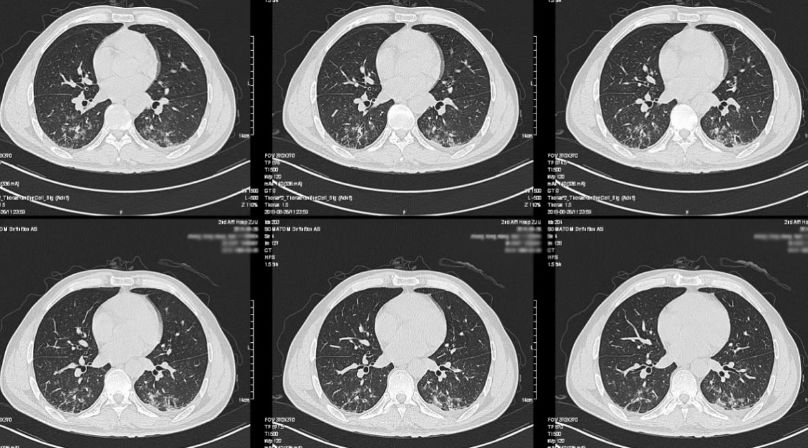

转入脑重症监护室后,予以斯沃600mg Q12H及美罗培南1g Q8H抗感染治疗,沐舒坦30mg Q12H化痰治疗,甘露醇125ml Q6H加强脱水降压、甲强龙80mg QD减轻水肿及泮立苏护胃等对症治疗。患者发热症状较前缓解(图10),于再入院后28日转回普通病房,查体:嗜睡状态,气管切开,双肺呼吸音粗,可闻及散在湿罗音,颈软无抵抗,腹部平软,无压痛反跳痛,左侧肌力5级,右侧肌力2级。复查头部CT示左额顶病灶继续增大(图11),胸部CT示肺部感染较前好转(图12)。

图12. 复查胸部CT提示肺部炎症较前减轻,胸腔积液较前吸收。